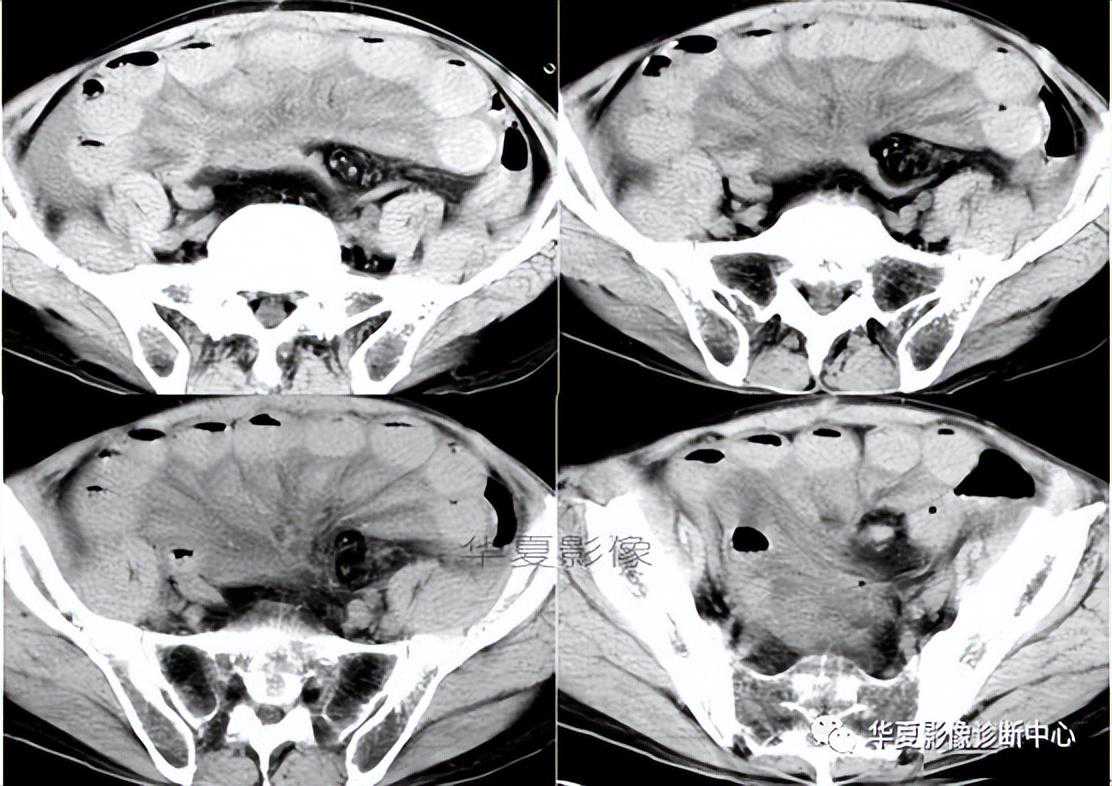

022:靶征(肠套叠)

是肠套叠最常见的特征性CT征像,为肠套叠长轴与CT扫描层面垂直时的表现,反映了套叠的各层肠壁、肠腔及肠系膜间的关系。典型排列为自外向内分别代表鞘部外层肠壁、鞘部肠腔内造影剂、鞘部内层肠壁、偏心性套入部肠系膜、套入部肠壁、套入部肠腔内造影剂。

肠套叠是指一段肠管及与其相连的肠系膜(套入部)被套如其相连的一段长管内(鞘部),导致肠内容物通过阻碍。婴儿由于大肠与小肠管径之比例相差大。故小肠易陷入大肠而被套牢。少数肠套叠可能来自某些器质性病变如美凯尔憩室、肠息肉、异位胰腺小结、血管瘤、异物、复制肠管、淋巴增生、肿瘤、寄生虫等,其中以美凯尔憩室最多,过敏性紫斑也常会合并肠套叠,大于2岁的小孩发生肠套叠,一定要考虑到这些病变。大于5岁的病例中,则以淋巴瘤为最多;成人肠套叠小肠多见,常伴发良性病变;结肠型肠套叠则更多由恶性病变继发。良性病变有脂肪瘤、平滑肌瘤、血管瘤、神经纤维瘤、腺瘤样息肉、美克尔憩室、术后粘连机场动力性病变等;恶性病变有转移瘤、腺癌、类癌、淋巴瘤及平滑肌肉瘤等。由于肠套叠长轴与CT扫描层面的角度不同,表现各异。如扫描层面和迂曲的肠道相平行时,表现为彗星尾征或肾形征:即套叠近端肠系膜血管牵拉聚拢的征象。

一般情况下,慧星尾征均与肾型肿块相伴出现。该肾形肿块为套鞘部游离缘与套入部近端肠管及肠系膜的CT斜切面图像,其中游离的套鞘呈弧形围绕套入部,形状若肾轮廓外形,而套入部近端肠管、肠系膜形状若肾蒂。此时,所谓慧星尾征的组成还应包括套入近端肠管。如果套叠的肠管与CT扫描垂直,则呈靶形征,即肿块影表现为圆形或类似环形。通常在肿块内可分辨出层样结构,推测可能是继发于套入部和鞘部间的液体或是肠壁水肿造成密度对比,类似同心圆形;当套入部肠壁显著水肿坏死或套入部肿瘤周围浸润累及肠系膜,肠系膜血管及脂肪、套叠时间较长,套入部系膜血管受挤压时,静脉血液回流障碍,套入部肠壁充血水肿、变硬,形成不完全性肠梗阻,套叠以上肠管蠕动增强,可引起代偿性肠管扩张肥厚,并可见肠系膜连同其血管纠集、扭曲,形成“漩涡征”。

成人肠套叠还有一些间接征象可帮助诊断,如肠壁不规则增厚或见密度不均匀的软组织块影,伴周围系膜及筋膜浸润、腹膜后淋巴结增大,则提示病因是恶性肿瘤。肿瘤所致肠壁水肿、坏死与部分炎症引起的套叠无法明确区分,肠壁及肠系膜血管有增厚伴肠壁内气体影的征象可提示血运障碍。如CT显示肠套叠直接征象、并伴随近段肠梗阻征象,则表示套入时间较长。如果套入部肠壁及鞘部组织发生水肿、变硬,形成不完全性肠梗阻,套叠以上肠管蠕动增强,可引起代偿性肠管扩张肥厚。